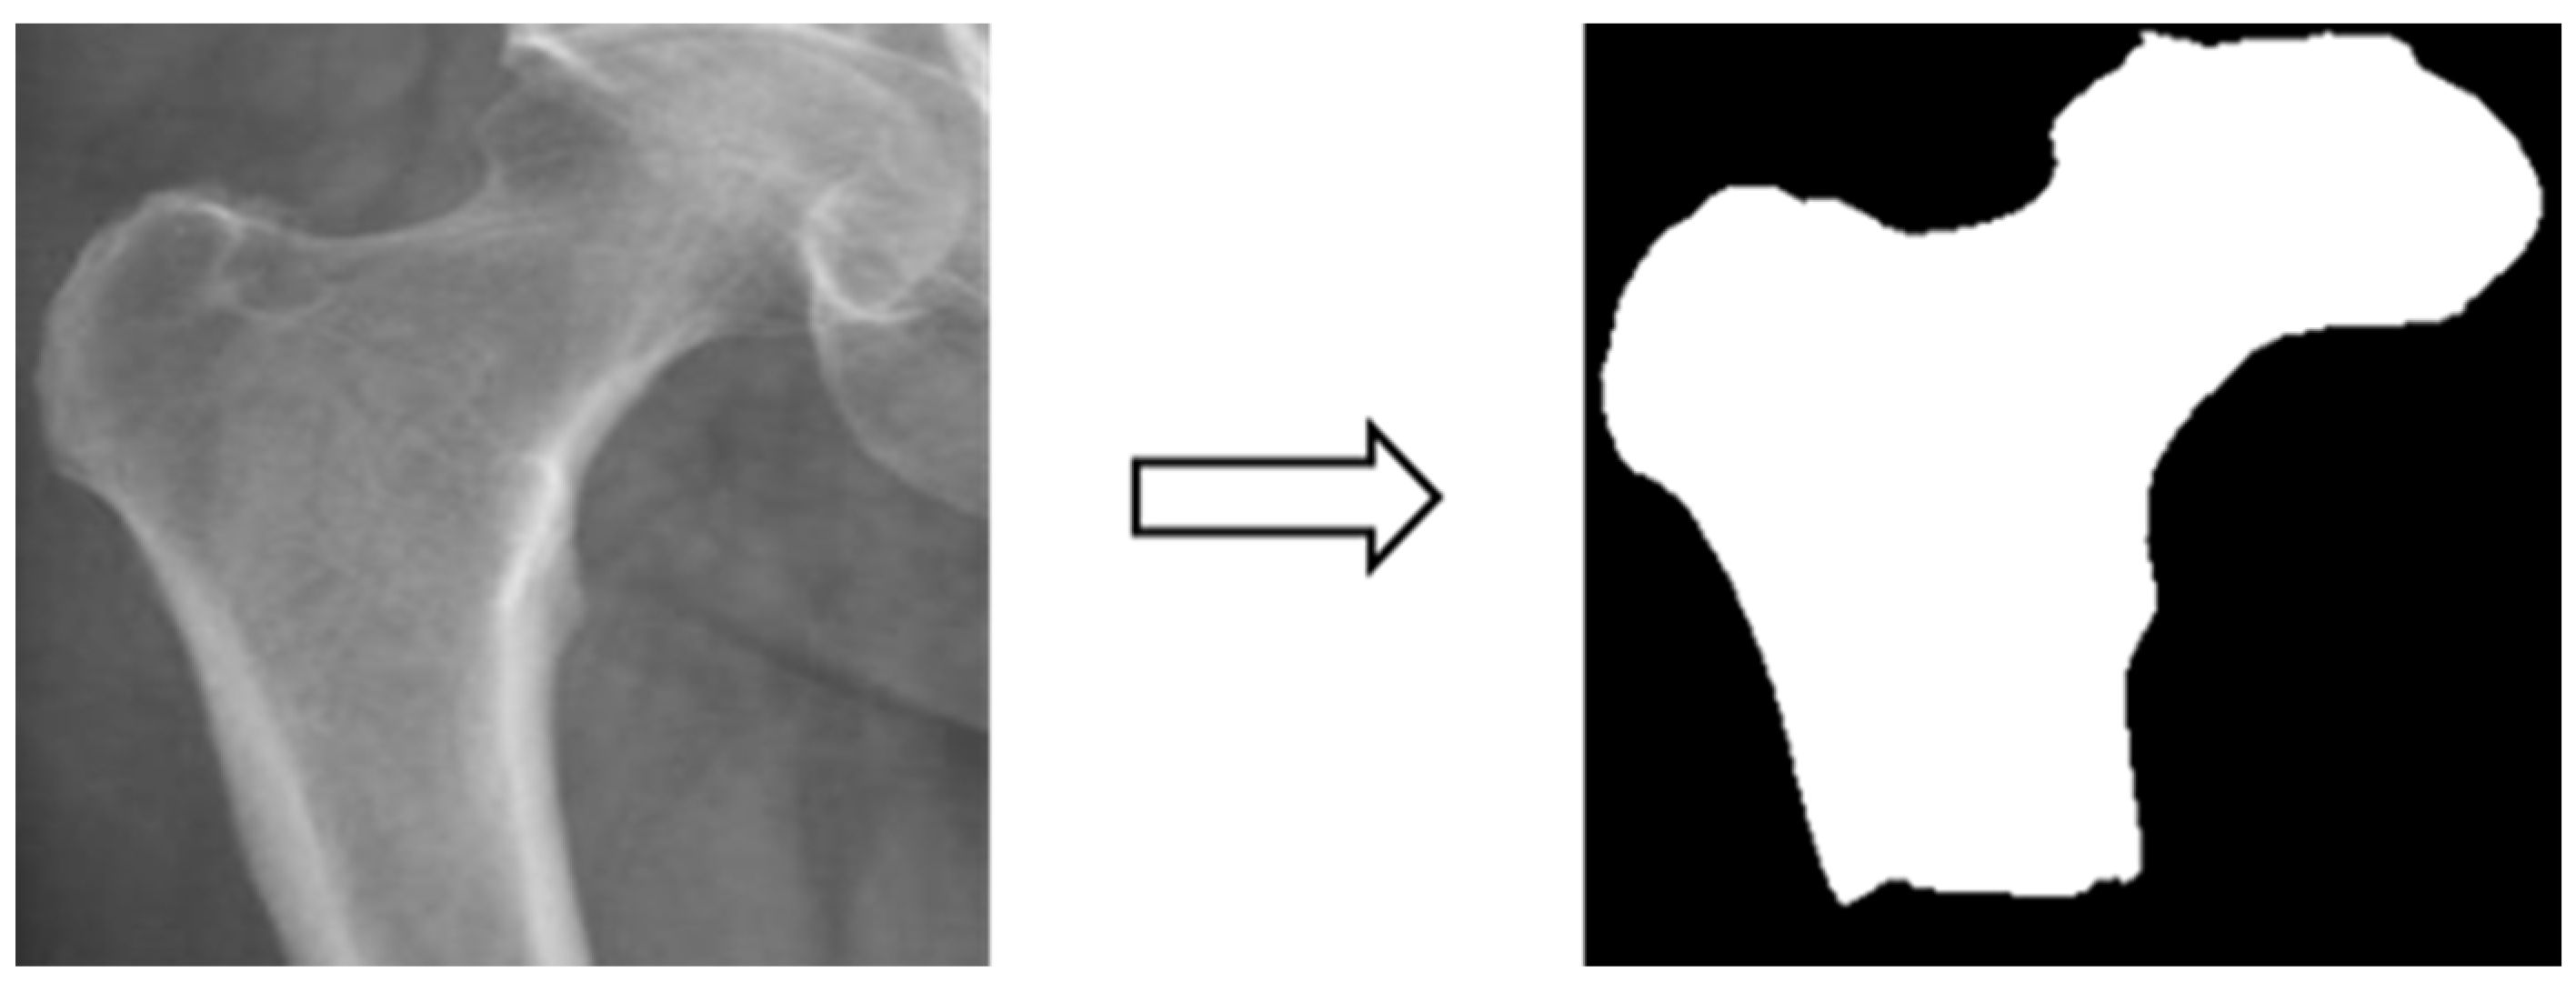

3.3.2. Image Segmentation

In this study, four parts of the image labeled X-ray images were used in image segmentation by feeding them into U-Net and U-Net++ models for training, and the bit depth of the four parts of the image was converted from the original 24 bits to 8 bits before the model training. The reason for choosing to use U-Net and U-Net++ is that their model structure is simpler, they do not need to spend a lot of time filtering out the remaining noise in the medical images, and they are less likely to form overfits for a small number of image datasets. The binary segmentation prediction results obtained after training the models of U-Net and U-Net++ are shown in Figure 3 below.

Figure 3.

Image segmentation.